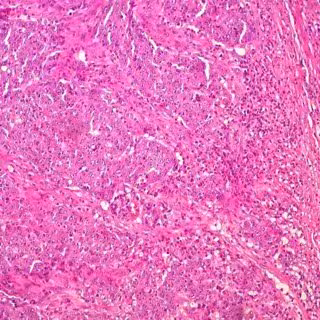

Cáncer de colon

Los casos de aparición temprana de cáncer colorrectal se han incrementado en los últimos años, siendo la mayor parte de posible origen ambiental y alrededor de un 20 por ciento de ellos de causa genética hereditaria conocida, según ha señalado el doctor José Perea García, del Servicio de Cirugía General de la Fundación Jiménez Díaz.